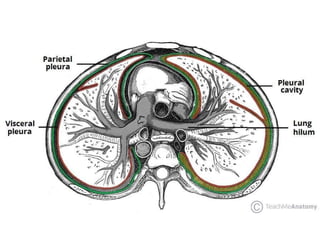

LAYERS OF THE PLEURA

• Two layers that are

contained by the

pleura:

• (a) Visceral pleura

• (b) Parietal pleura.

• Pleural Cavity is

a potential space

between the

viscera and

parietal pleura.

Structure of the Pleurae

• Each pleura can be divided into two

parts:

• Parietal pleura – covers the internal

surface of the thoracic cavity.

• Visceral Pleura

• Covers the lungs.

• The visceral pleura covers the outer

surface of the lungs, and extends into

the interlobar fissures.

Pleural Cavity

• The pleural cavity is a potential space

between the parietal and visceral pleura. It

contains a small volume of serous fluid,

which has two major functions.

• It lubricates the surfaces of the pleurae,

allowing them to slide over each other.

• The serous fluid also produces a surface

tension, pulling the parietal and visceral

pleura together.